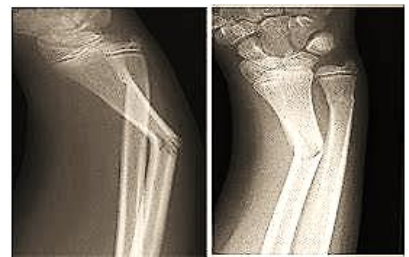

J.P.L., 5 anos, masculino, acompanhado pela mãe, dirigiu-se a um Centro de Reabilitação local para

tratamento de fratura. A imagem radiológica portada pela mãe está apresentada abaixo.

Após avaliação cinético funcional seguida de exames complementares, conclui-se tratar-se de